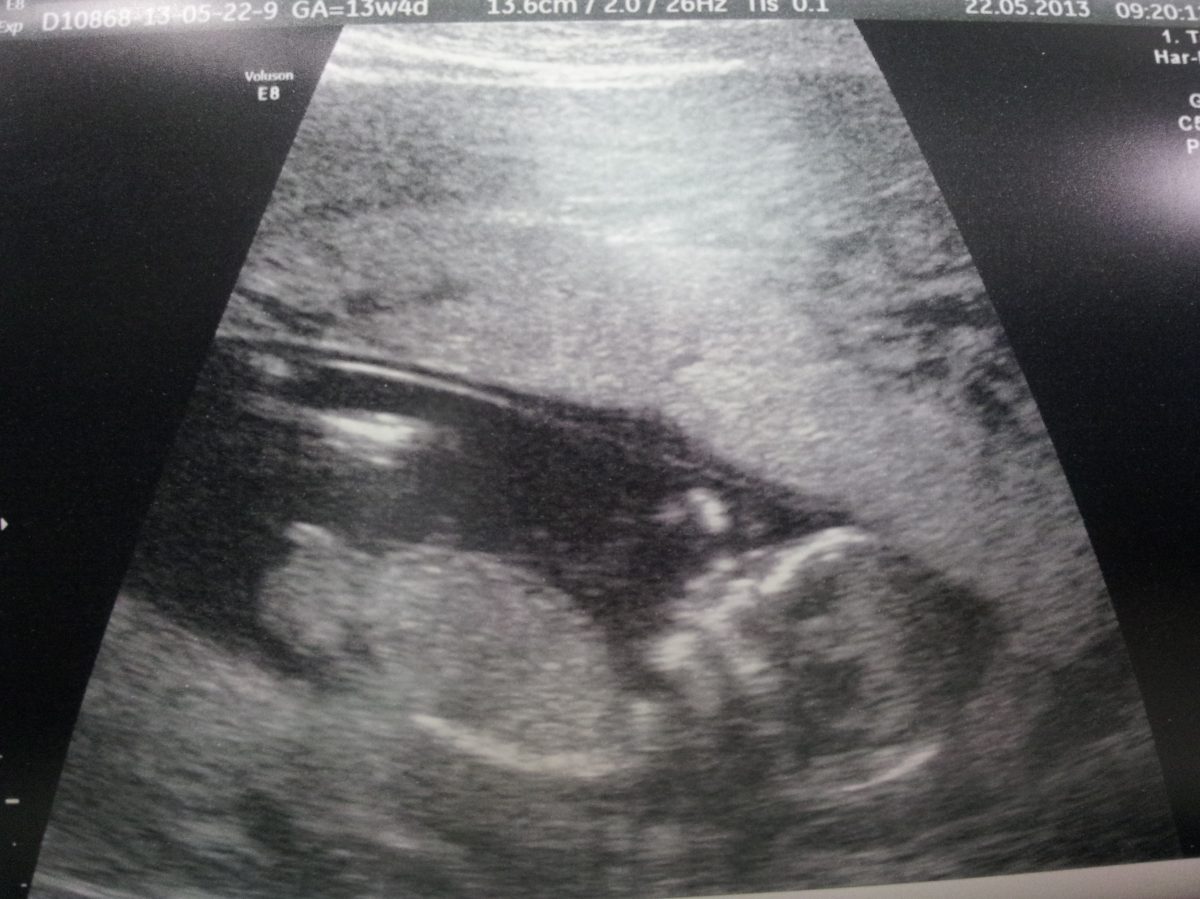

Fotografie (Slůně)

Fotografie (Slůně). Zdroj: archiv redakce